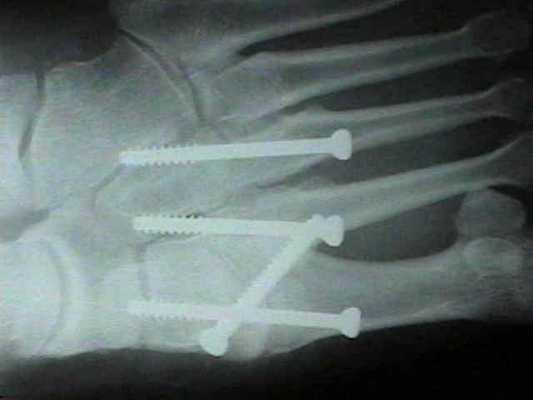

При прогрессивном коллапсе сводов стопы, хронической нестабильности, прогрессивном наружном смещении переднего отдела стопы рекомендуется артродез всего суставного комплекса Лисфранка. Существует много вариантов выполнения данного вмешательства, с использованием спиц, винтов, скоб и пластин, в зависимости от оснащённости операционной и предпочтений хирурга. После операции потребуется 6 недель гипсовой иммобилизации, полную нагрузку можно давать не ранее 10 недели.

В ряде случаев целесообразно применить смесь хирургических техник. Если рассматривать весь сустав Лисфранка разбив на внутренний, центральный и наружный отделы, то его внутренний (1) и латеральный (4-5) отделы подвижны, хотя и с малой амплитудой, а центральный (2-3) практически не подвижен. По этой причине в хирургической практике часто используется неполный артродез, то есть выполняют артродез 2-3 предплюсне-плюсневых суставов а 1,4,5 временно фиксируют спицами.

После осмотра в отделении ортопедии №2 ГКБ №13 принято решение о проведении операции - открытому устранению вывиха, артродезе 1-2-3 плюсне-клиновидных суставов, 1 межклиновидного сустава при помощи винтов и пластины, трансартикулярной фиксации спицами 4-5 плюсне-клиновидных суставов.

В такой ситуации остаётся один выход - операция. Необходимо освободить от рубцовых тканей весь сустав Лисфранка - а это как минимум 5 предплюсне-плюсневых суставов, вернуть плюсневые кости в нормальное положение, и зафиксировать 1-2-3 предплюсне-плюсневые суставы винтами и или пластинами, а 4-5 спицами, которые через 6 недель будут удалены.